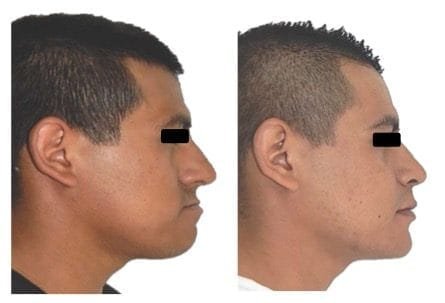

Fotografías extraorales: se observa la corrección de las relaciones esqueléticas maxilo mandibulares. La asimetría facial que presentaba el paciente que proyectaba su mandíbula hacia la derecha y la hipoplasia maxilar mediante se corrigió mediante la osteotomía Lefort I alta con 8 mm de avance, la proyección malar se mejoró con los injertos nasogenianos, la proyección excesiva de la mandíbula y el mentón se mejoró con una genioplastia de avance de 6 mm, se obtuvo un adecuado balance del perfil y simetría facial con una sonrisa amplia y espacios negativos disminuidos. (Figs. 14)

Fig. 14. Fotografías extraorales finales: A) Frente. B) Sonrisa. C) Perfil.

Imágenes comparativas pre y postratamiento

Imágenes extraorales de perfil: se nota un perfil más recto y estético son prognatismo. (Figs. 18)

Fig. 18. Fotografías comparativas extraorales de perfil ante y postratamiento.